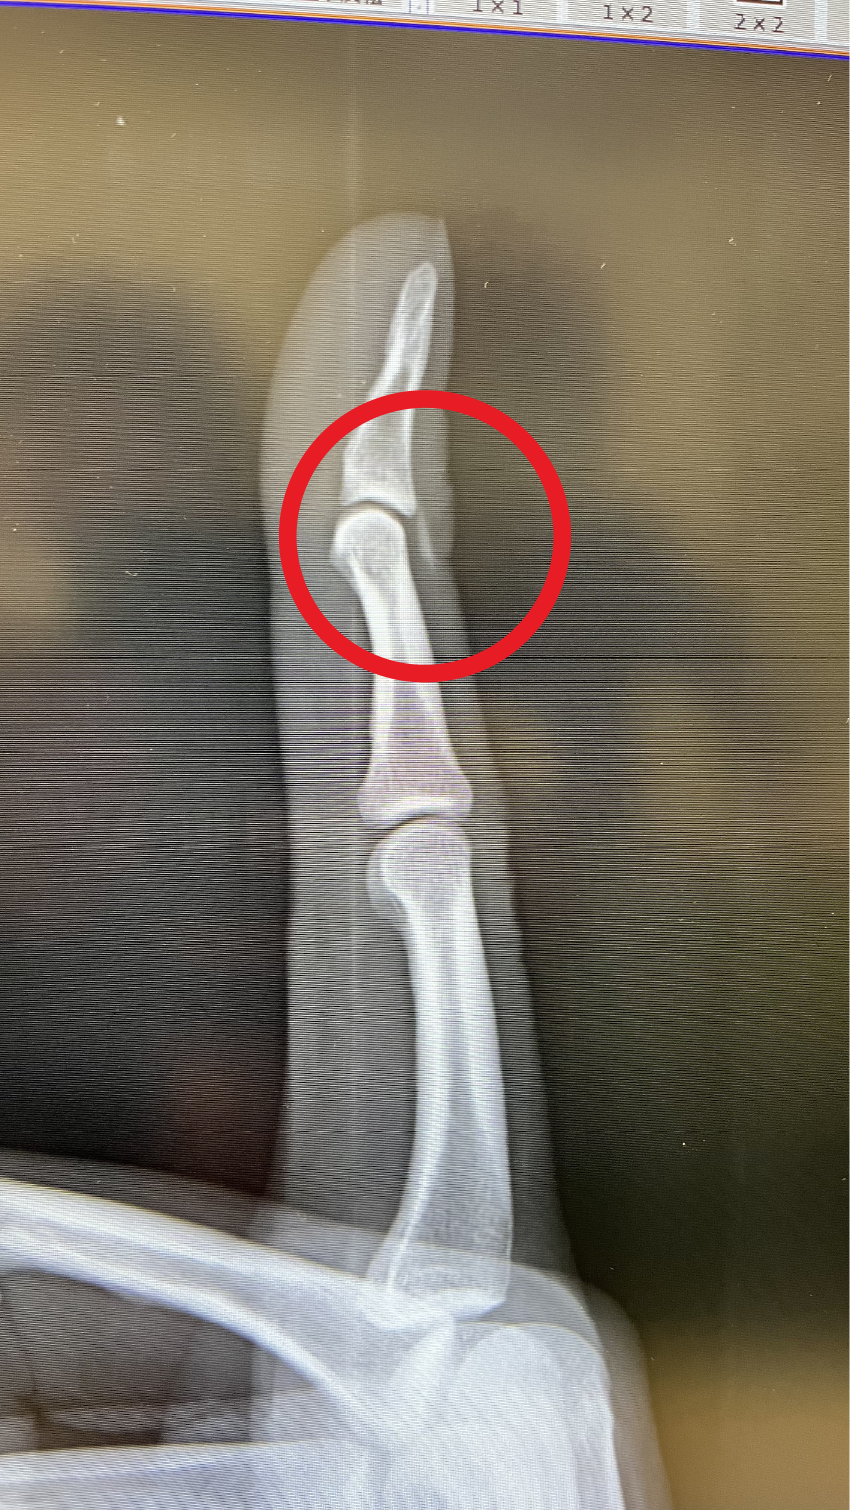

その時のレントゲンがこちらです。

見事に鯛の背びれのトゲがブッ刺さってます。

これをドクターが見事にぐりぐりと傷口を広げながら無事にピンセットで抜いてくれました。私の指は元通り曲がるようにすぐになりました。

刺さったのはちょうど手の甲側、人差し指の第一関節、そこから約八ミリ先に5ミリほどの硬いものが確認できます。

どうやらトゲが折れて指の中に残ってしまっているようです。